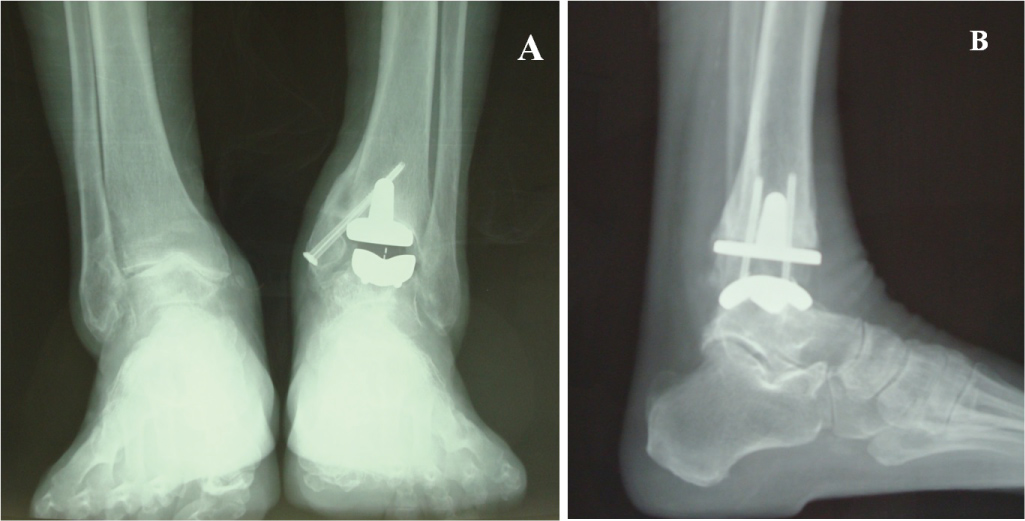

Lucencies were not seen in any of the zones around the talar component. Radiographs showed subsidence of the talar component < 5 mm in 3 ankles and a subsidence between 5 and 10 mm in 2 ankles (Figure 4). None of these 5 patients were associated with a clinical correlation in the radiographic finding. There were no cases of tibial component mobilization and migration. A periprosthetic asymptomatic cyst was detected in 1 patient with posttraumatic arthritis. The cyst was located in the medial zone [14] of the tibial component two years postoperatively (Figure 5). We observed a posterior osteophyte overhanging distally from the tibial plafond in 3 primary osteoarthritis ankles.

Figure 4: Radiographs showing subsidence of the talar component and radiolucency around the talar component. A) Lateral view; B) AP view. View Figure 4